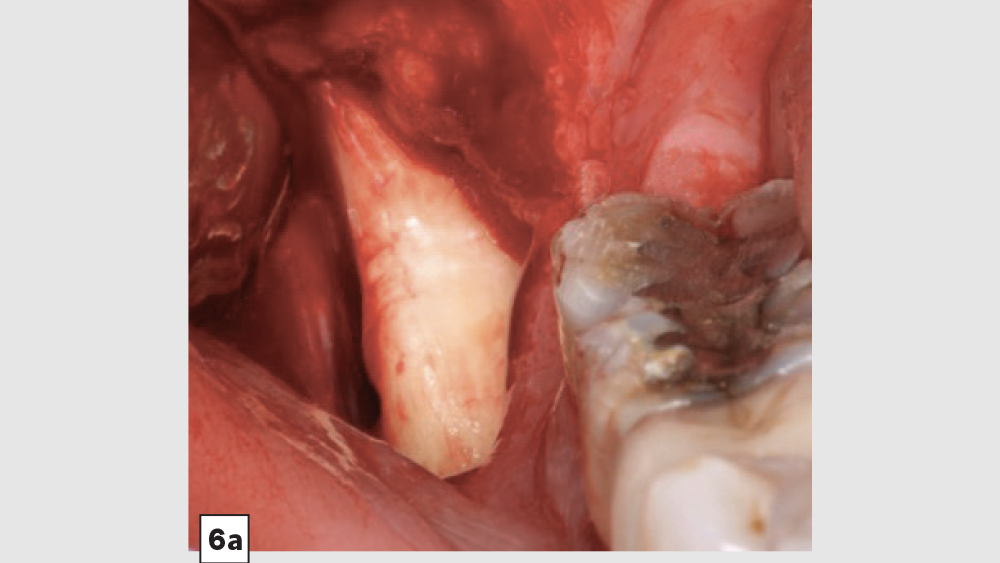

a. Mandibular Ramus Donor Site — The “Scraping Technique”: One option to obtain autogenous bone is to expose the mandibular ramus and remove bone from the external oblique ridge with double-action rongeurs (Figs. 6a, 6b). The “scrapings” may be placed in a surgical bowl with sterile saline. Ramus block grafts may be harvested; however, the blocks need to be reduced into smaller pieces, which is rather time-consuming. Additionally, a ramus block graft (i.e., veneer graft of the lateral ramus) has a higher surgical morbidity and far greater post-op complications.

Figure 6a

Figure 6b

Figures 6a, 6b: Ramus autogenous graft: mandibular ramus exposed (6a), scrapings harvested with double-action rongeurs (6b).